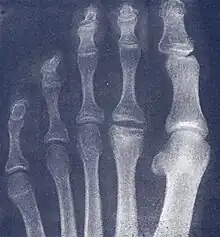

Freiberg disease as seen on plain film

X-ray of Freiberg disease

2. Radiography: X-rays may reveal flattening, sclerosis, or fragmentation of the metatarsal head.